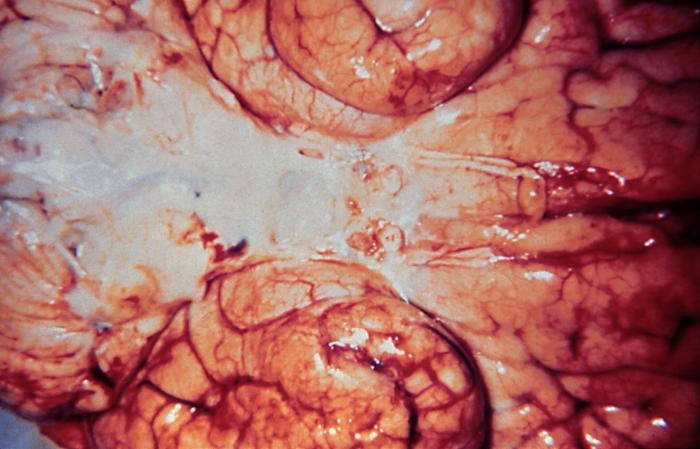

It is a highly fatal infectious disease that affects the brain and is caused by close contact or sharing of utensils. The annual death toll stands at around two million. It can be prevented by vaccines and antibiotics including penicillin but often five to ten percent patients die even after treatment.